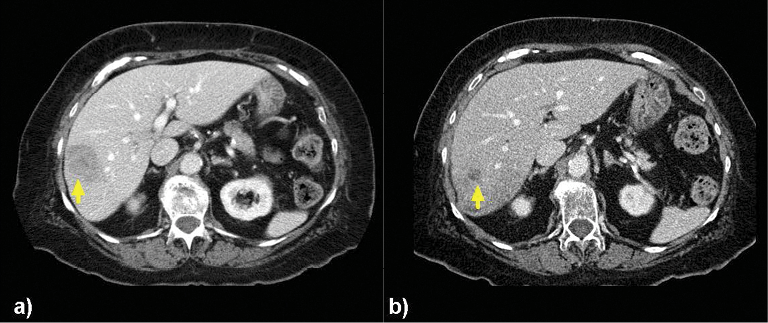

New research on the minimally invasive, image-guided therapy Yttrium-90 (Y-90) radioembolization shows promise in treating breast cancer that has spread to the liver when no other treatment options remain.

Researchers determined that the tumors got smaller or remained stable in 98.5 percent of the patients after radioembolization, while tumor reduction of more than 30 percent occurred in 24 patients. Additionally, these women experienced no major side effects.

In Y-90 radioembolization, an interventional radiologist guides a catheter into the hepatic artery that supplies blood to the liver. Microbeads containing radioactive Y-90 are then injected and float downstream to deliver cancer-killing radiation inside the heart of the tumor.

In the past, Dr. Lewandowski explained, Y-90 radioembolization has been used to successfully treat primary liver cancer and metastatic colon cancer. “Because of the success of radioembolization in these settings, we are starting to see interventional radiologists being asked more and more to treat patients who have other cancers that have spread to the liver,” Dr. Lewandowski said. “The liver is a very prevalent area of metastatic disease, and breast cancer is an important source."